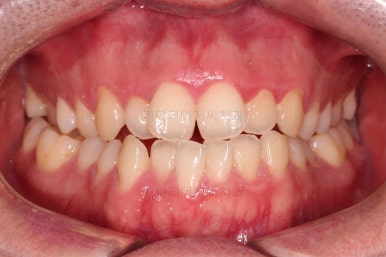

부산긴얼굴긴턱교정 전후 비교해 볼게요.

이렇게 비교해 놓으니 더 드라마틱하죠.

당연히 교합/위아래 폭 등 치열이 좋아졌고요.

얼굴 모습에서도 주걱턱이 개선되었고, 긴얼굴, 긴턱 등 길이 부분도 굉장히 좋아졌습니다.

적절한 협진을 통해서 과하지 않게 특유의 양악수술 느낌의 어색함 없이 개선이 잘 되었습니다.

얼굴 길이가 짧아지면 이렇게 훨씬 어려보이는 효과도 주게 됩니다.